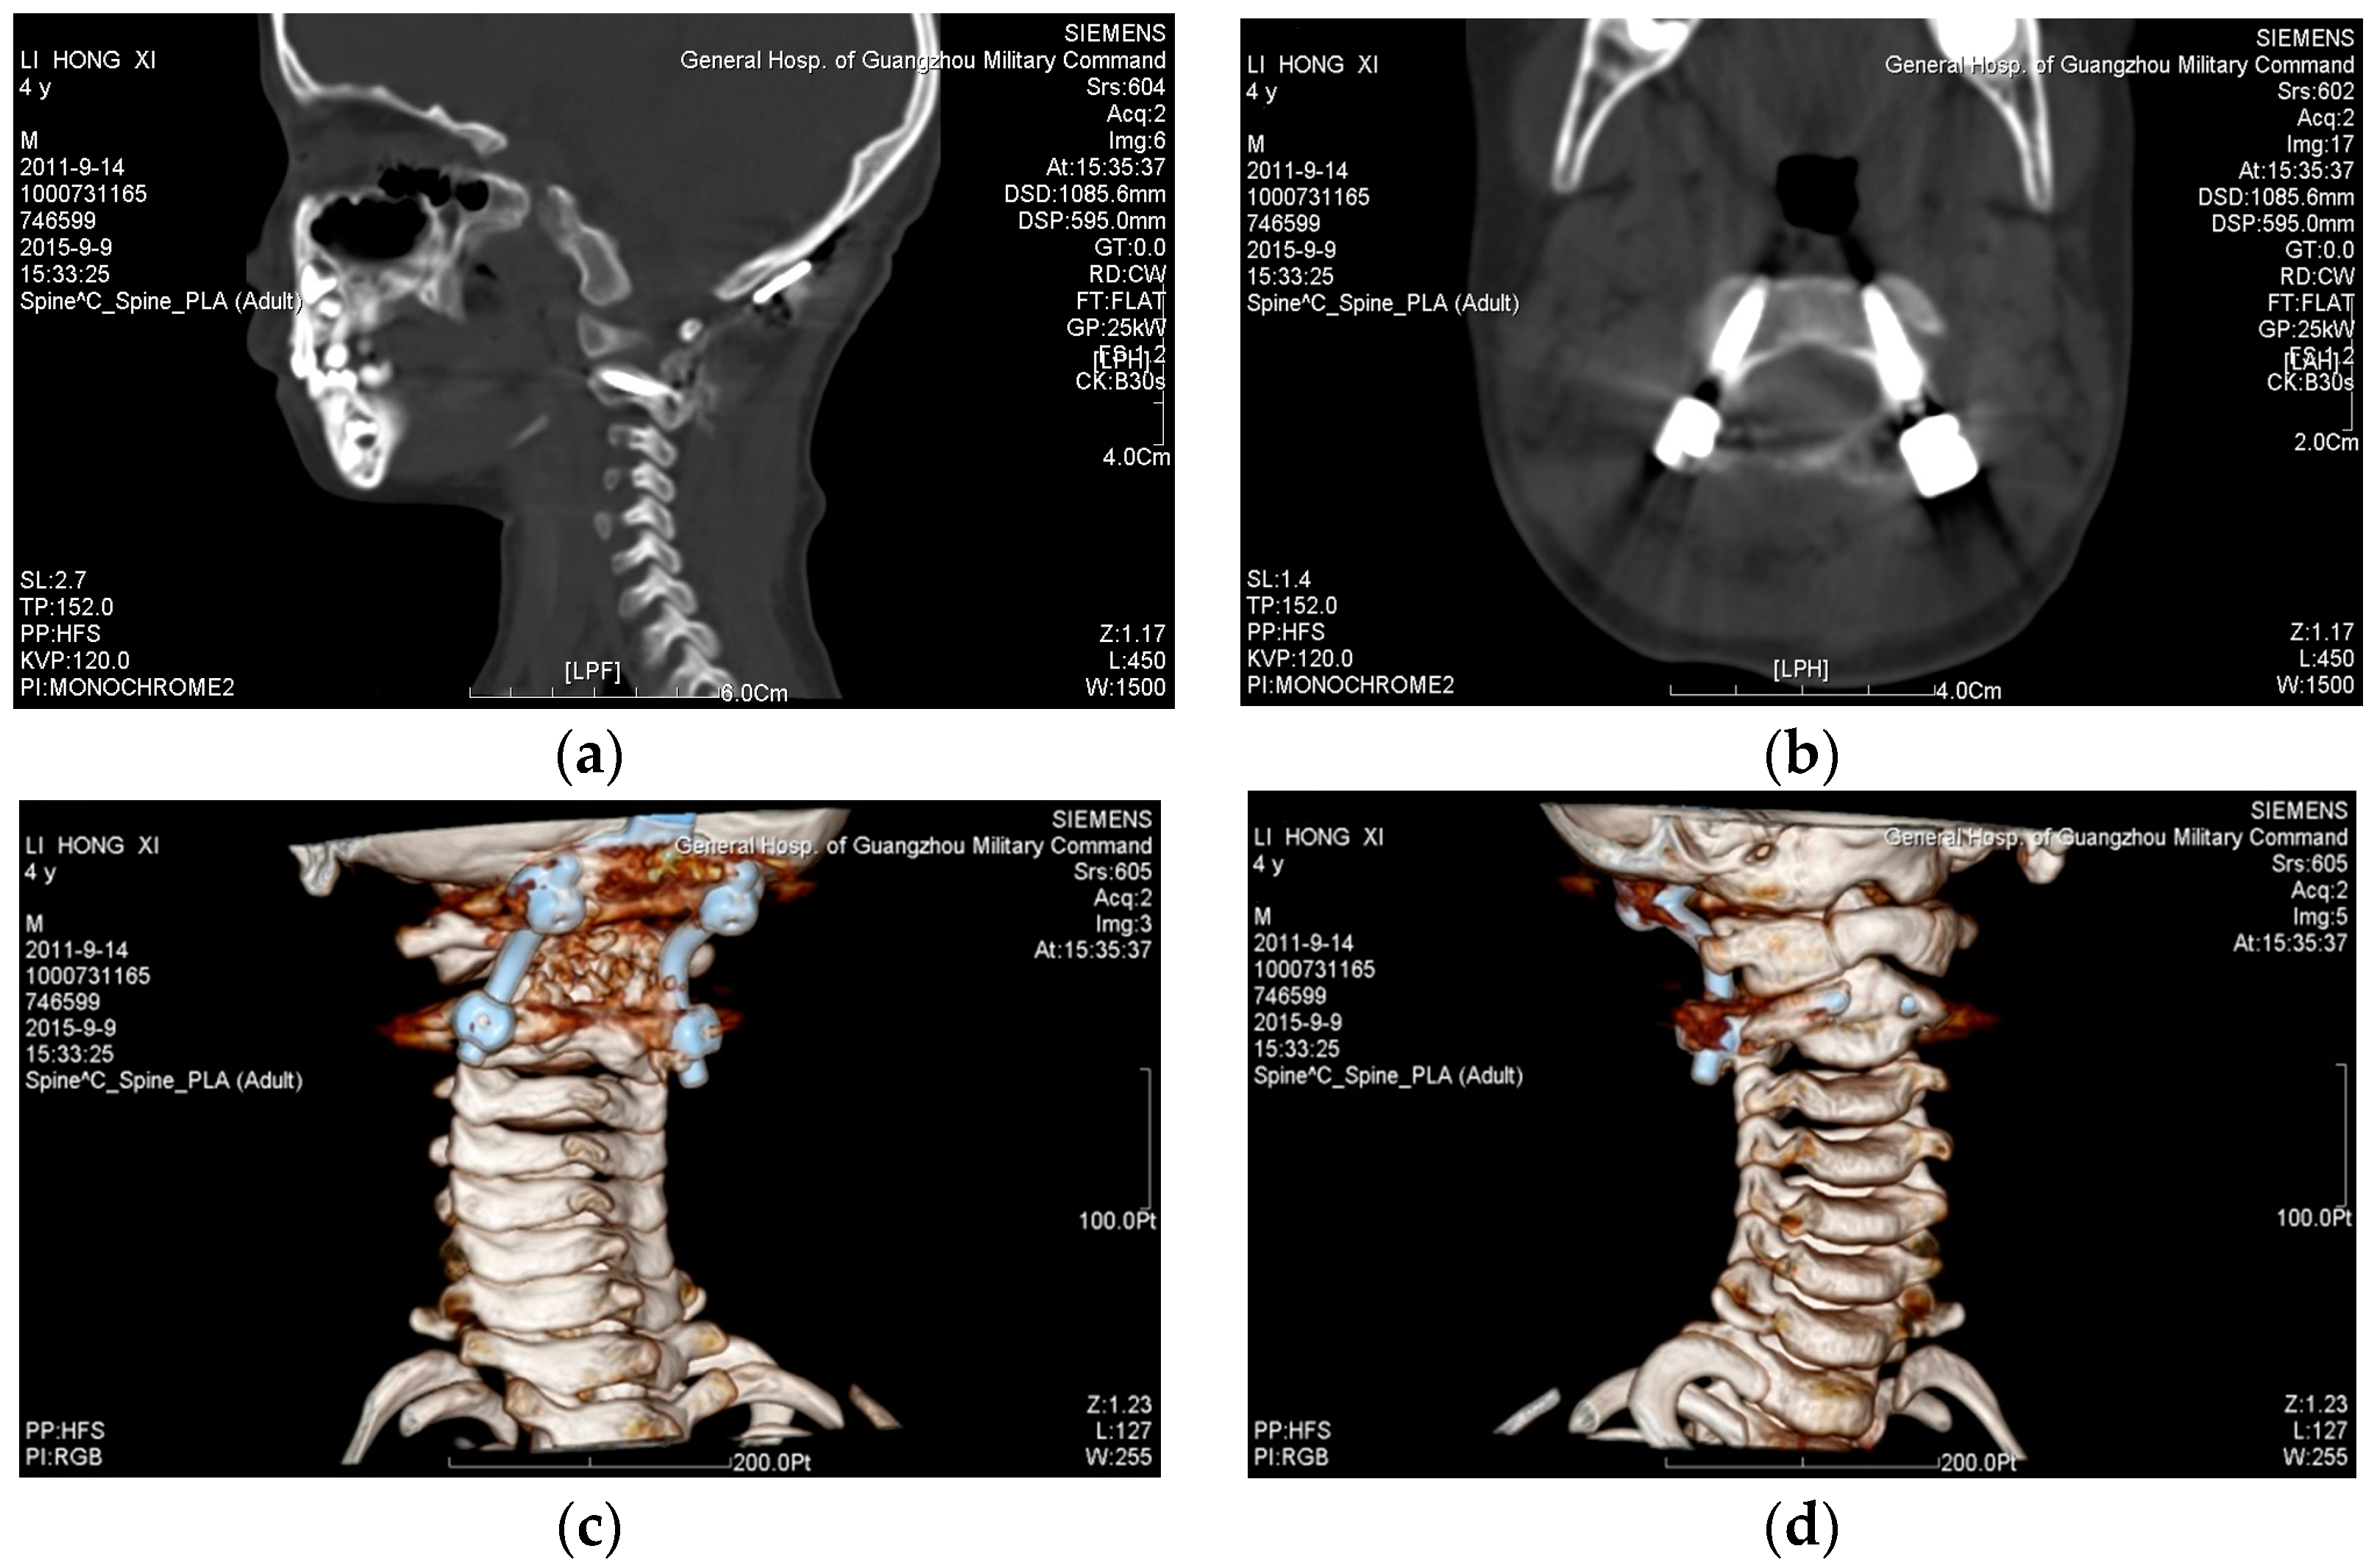

- The Biograph 64 PET/CT apparatus (SIEMENS, Munich, Germany) was used to obtain scan data, with a scan condition of 120 kv,150 mAs; scan slice thickness of 0.5 mm; and a scanning time of 10–15 s. The factor that affects the geometrical accuracy is the scan slice thickness, which would impact the surface fitting accuracy. The data from a thin-layer CT scan of the cervical vertebrae of the patient was imported into Mimics 16.0 (Materialise, Leuven, Belgium) to extract the target spine. Store this as STL (binary) to be imported into Geomagic software (3D syestems, Rock Hill, SC, USA). Elimination of the noise points inside the bone to obtain the 3D entity was accomplished by executing the following process: extract surface—construct patches—construct grids—surface fitting, and store it in the STEP AP203 format; import the data from Geomagic software into SolidWorks software; and integrate the separate 3D entity models into an assembled model to obtain the target spine model (as shown in Figure 1a).